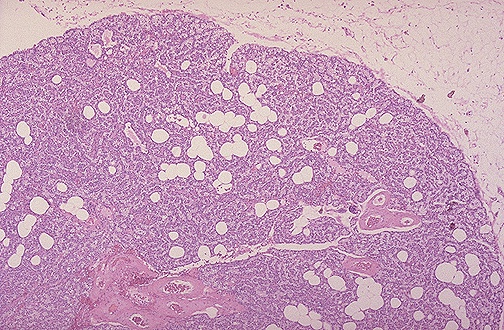

At low magnification, the normal parathyroid gland is seen to be an admixture of endocrine cells and some

adipose tissue

.